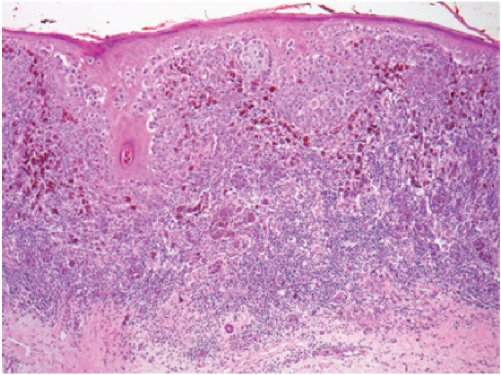

Very high magnification micrograph of tumor infiltrating lymphocytes, abbreviated TILs, in a case of colorectal carcinoma. TILs may also be spelled tumour infiltrating lymphocytes. H&E stain.